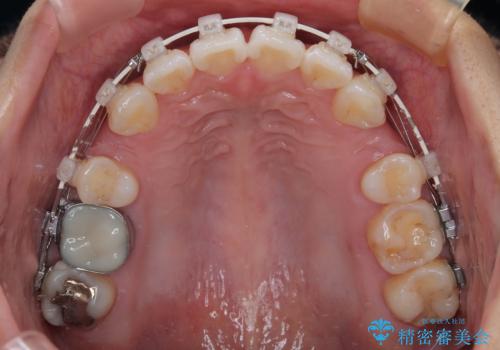

- 矯正装置

- 審美装置

- 前歯が突出して、眠るときに口が開いてしまうことを気にして来院された患者様です。

横から見た際の口元の飛び出した印象も改善したいとのことで、上下左右の第一小臼歯4本を抜歯し、ワイヤー装置にて抜歯矯正を行うこととしました。